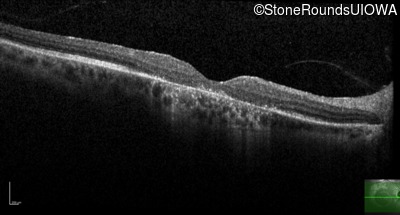

Optical Coherence Tomography - Right - 10/100 -2 sc

Exemplar / OCT Stack